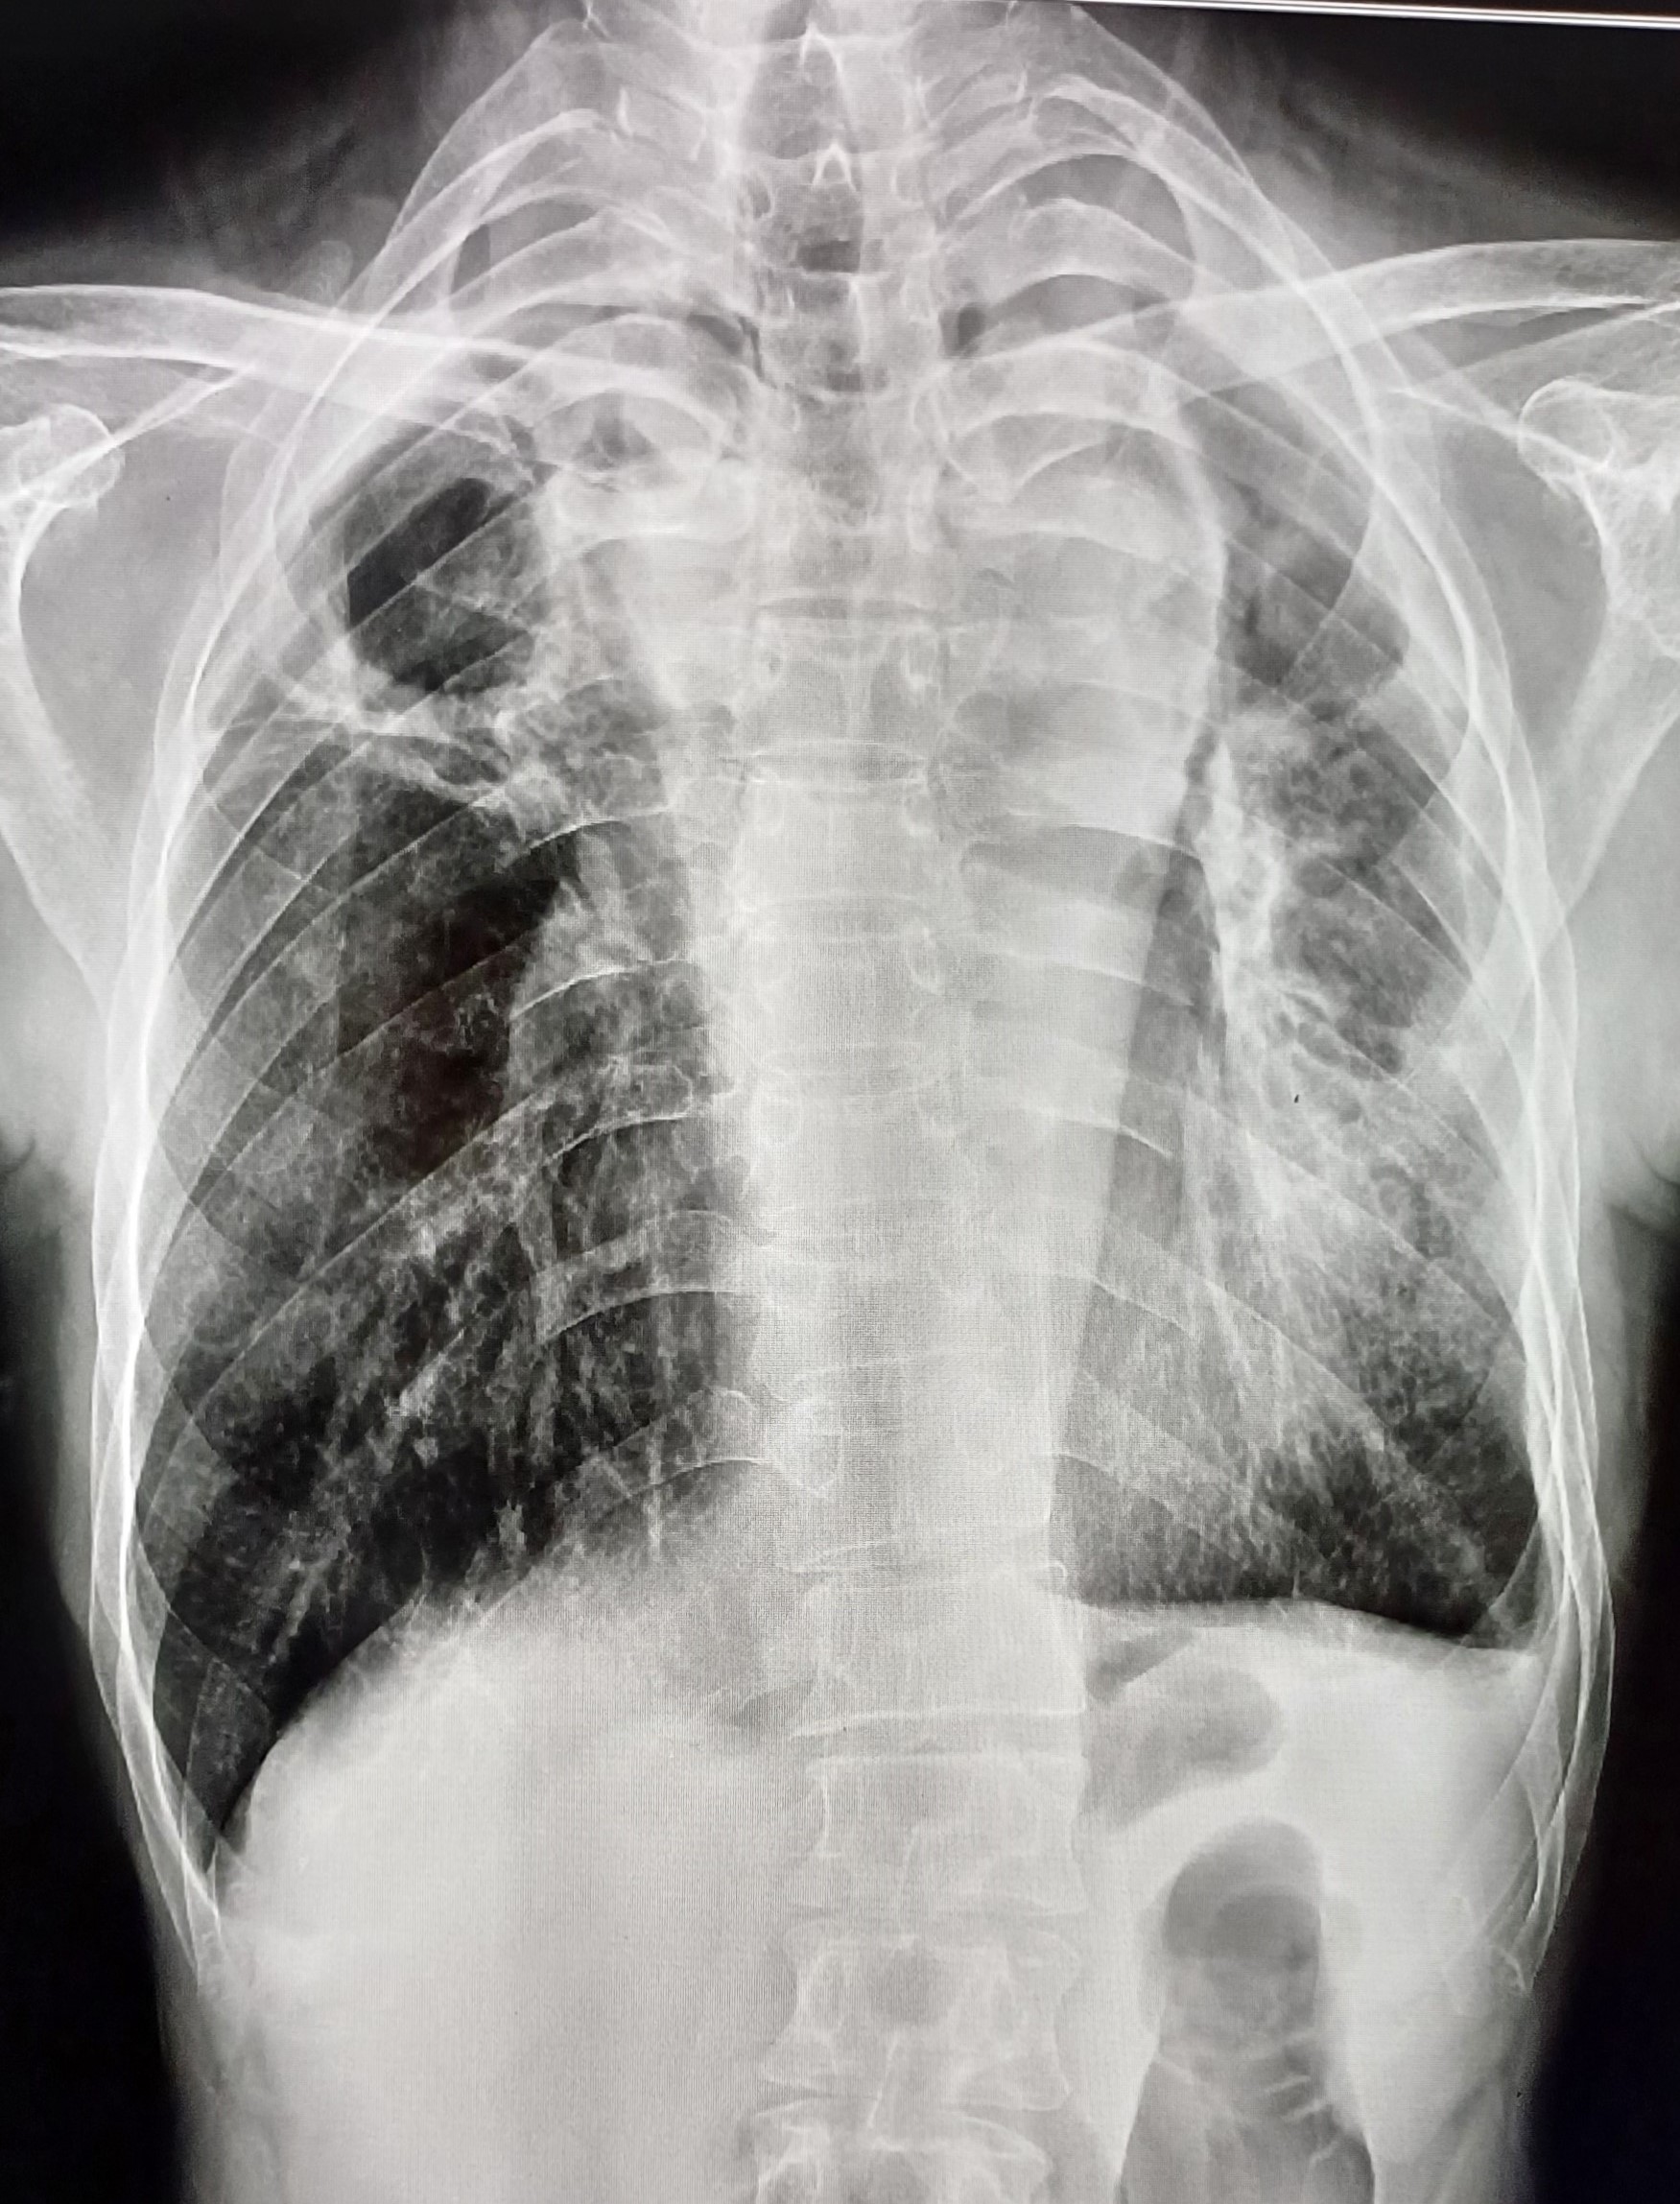

| 7 | IGGMC, Nagpur, Nagpur | P2 | 29-4465 | Ibrahim Pathan | Consent taken on Paper | 21 Yrs. |

Provisional Diag : Pleural Effusion ?

Final Diag : Tubercular Pleural effusion (Clinically Diagnosed Tubercular Pleural effusion) |

TB Case (Confirmed) | Right sided pleural effusion | Abnormality visible on x-ray |

View |